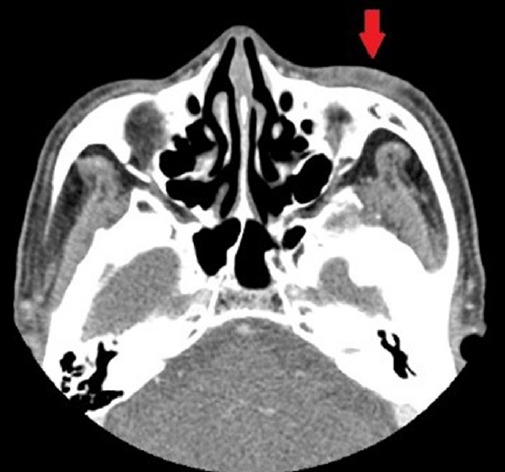

Primary cutaneous mucinous carcinoma (PCMC) is a rare malignant neoplasm that originates from the deepest part of the eccrine sweat glands. Characterized by slow growth, PCMC often appears on the head and neck of older patients. Although it rarely metastasizes, its high recurrence rate leads to significant morbidity. Clinically differentiating PCMC from benign tumors is challenging due to its slow growth and asymptomatic nature, and a biopsy is often required for a definitive diagnosis. A 77-year-old man presented with a non-tender lesion on his left lower eyelid that had been gradually progressing over a decade. The lesion was excised, and histological examination confirmed it as PCMC. A positron emission tomography-computed tomography scan conducted to differentiate between primary and metastatic cancer showed no abnormal findings. Computed tomography was then performed to assess the remaining primary site, followed by a wide excision. The frozen biopsy revealed no cancer in the margins from five directions; however, the permanent biopsy confirmed the presence of cancer in the base margin. After consultation with the hematology-oncology department, the patient underwent additional radiation therapy. One year post-surgery, there were no signs of recurrence.